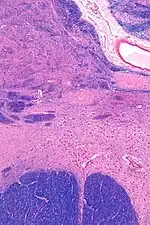

![]() MRI showing a coronal plane of the head with marks showing the location of the substantia innominata, the region in which the nucleus basalis is found. | |

The nucleus basalis in humans is a somewhat diffuse collection of large cholinergic neurons in the basal forebrain.[2] The main body of the nucleus basalis lies inferior to the anterior commissure and the globus pallidus, and lateral to the anterior hypothalamus in an area known as the substantia innominata.[1] Rostrally, the nucleus basalis is continuous with the cholinergic neurons of the nucleus of the diagonal band of Broca.[1] The nucleus basalis is thought to consist of several subdivisions based on the location of the cells and their projections to other brain regions.[2] Occasional neurons belonging to the nucleus basalis can be found in nearby locations such as the internal laminae of the globus pallidus and the genu of the internal capsule.[1]